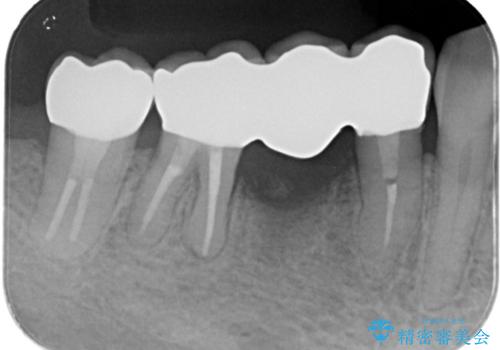

コアごと脱離して来院し、フェルールの獲得が厳しいためコアが立てられないので抜歯することになりました。

インプラントとブリッジの治療を提案し早く噛めるようにしてほしいという要望があったためブリッジにて治療をすることになりました。